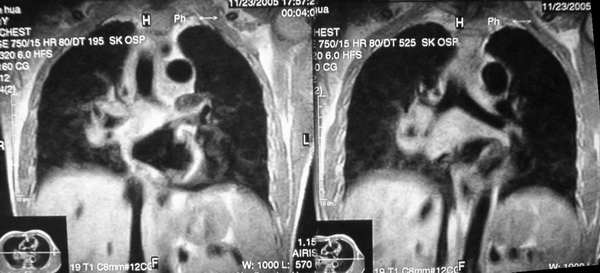

男,42岁。半年前体检发现右侧肺门肿大,mri示右侧肺门淋巴结肿大。腰背部疼痛伴右腿麻木1月入院。腹部b超示肝、胆、胰腺、脾、肾、前列腺及膀胱未见异常。afp、cea、ca199均正常。

胸部mri是半年前的,而胸部 增强ct是目前的,二者变化不大,肺部好像也没啥。

增强图像显示不清,好像有肺门及纵隔与腋下淋巴结肿大,右侧胸腔积液,腰1椎体骨质破坏,椎旁软组织肿块形成,其后硬脊膜囊明显受压。考虑淋巴瘤可能。其他待排。